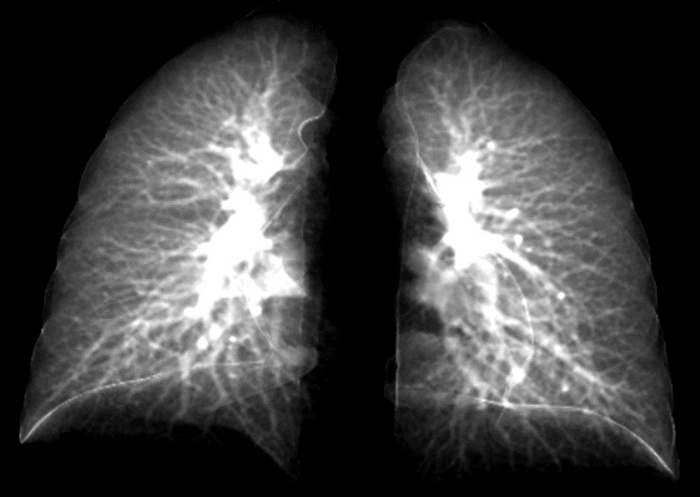

IMAGE: UNIVERSITY OF IOWA RESEARCHERS HAVE CREATED AN ADVANCED MODEL THAT CAN DETECT LUNG DAMAGE IN LONG-COVID PATIENTS USING A SIMPLE CHEST X-RAY. THE MODEL TAKES DATA POINTS FROM 2D LUNG IMAGES CONSTRUCTED FROM 3D CT LUNG SCANS. THIS IMAGE SHOWS DETAILS OF THE LUNG IN A 2D IMAGE. THE MODEL IS ATTRACTIVE, BECAUSE 2D CHEST X-RAY EQUIPMENT IS MORE COMMONLY AVAILABLE AND LESS COSTLY. view more

CREDIT: CHING-LONG LIN LAB, UNIVERSITY OF IOWA

That may change. In a new study, researchers at the University of Iowa have developed what is called a contrastive learning model. This model “learns” from composite 2D images constructed from 3D CT images to detect compromised lung function in long-COVID patients. Another technique, called transfer learning, then conveys lung diagnostic information from a CT scan to a chest X-ray, thus allowing chest X-ray equipment to detect abnormalities the same as if those patients had used a CT scan.

“The new element to the model is taking information from 3D CT scans showing lung volume and transferring that information to a model that will show these same characteristics in 2D images,” says Ching-Long Lin, Edward M. Mielnik and Samuel R. Harding professor and chair of the Department of Mechanical Engineering in the College of Engineering at Iowa. “Clinicians would be able to use chest X-rays to detect these outcomes. That’s the bigger perspective.”